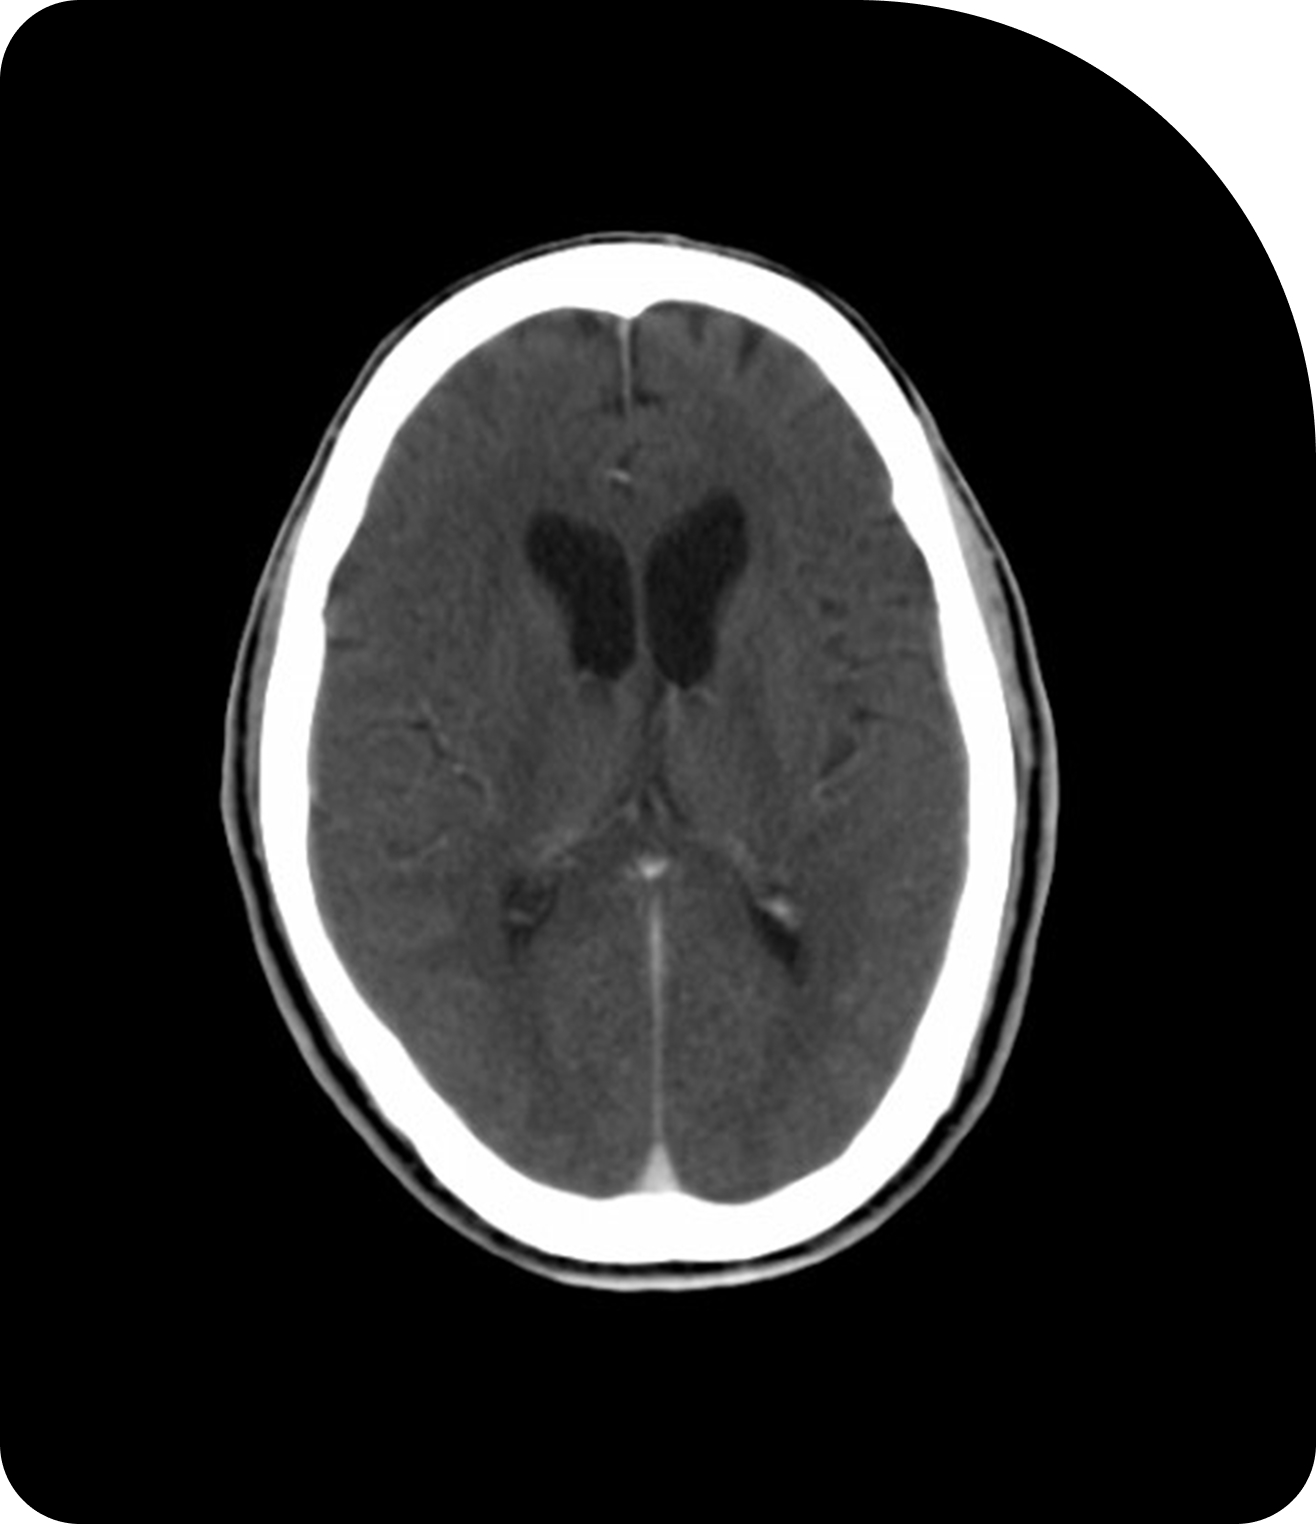

| Cerveau (gliome de haut grade) | UNITED (NCT04726397) ET UNITED-3 (NCT05720078) | Sunnybrook Health Sciences Centre | Faisabilité démontrée des réductions de marge importantes (40-71 %) grâce à la radiothérapie adaptative IRM-Linac. UNITED-3 passe à une thérapie adaptative en deux phases pour le glioblastome.[3] |